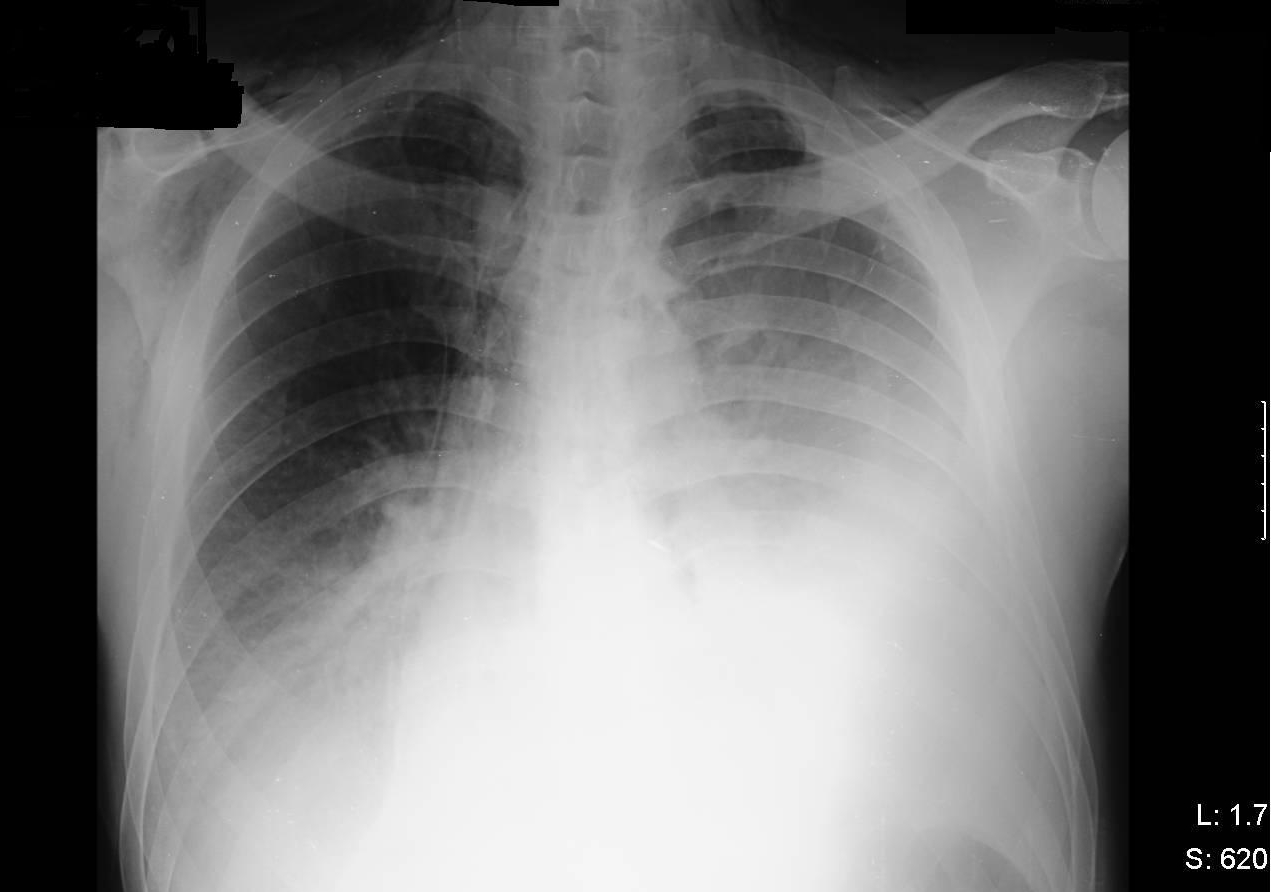

Peripheral WBC count = 14,000/cubic millimeter, and  the chest x-ray (fig. 1) showing bilateral air space disease, left pleural effusion, pneumomediastinum and subcutaneous emphysema. Review of the admission CXR revealed air in the soft tissue of the neck on the right side

Figure 1

Figure 1: Chest X-Ray hospital day 2

What is the main abnormality on this chest radiograph (Figure 3)?

Figure 3

(c) Left sided pleural effusion, subcutaneous emphysema and pneumomediastinum.

Chest x-ray is abnormal in 90% of cases of esophageal perforation but can be normal if taken early (3). Pneumomediastinum may be seen as demonstrated above by the radiolucent streaks of free air surrounding the trachea.